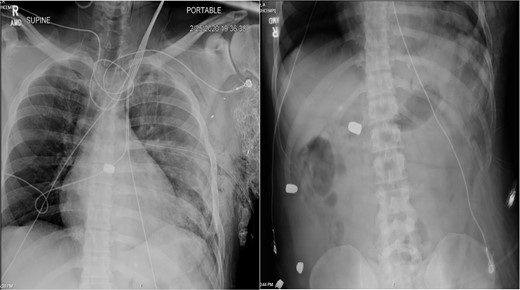

On hospital Day 7, the patient had acute hypoxic respiratory failure. CT chest found a right segmental pulmonary embolism and a retained bullet near the aortic root. A TEE was repeated, this time demonstrating severe aortic insufficiency (Fig. 4), and a bullet in the left coronary cusp. Cardiothoracic surgery was consulted for evaluation and management. The next day, the patient went to the OR for median sternotomy, cardiopulmonary bypass, aortic root repair with patch, re-attachment of the left coronary cusp, and removal of the bullet from the aortic root.

TEE with intracardiac bullet, severe aortic insufficiency. The bullet is labeled by an asterisk, with shadow artifact posterior to the bullet.